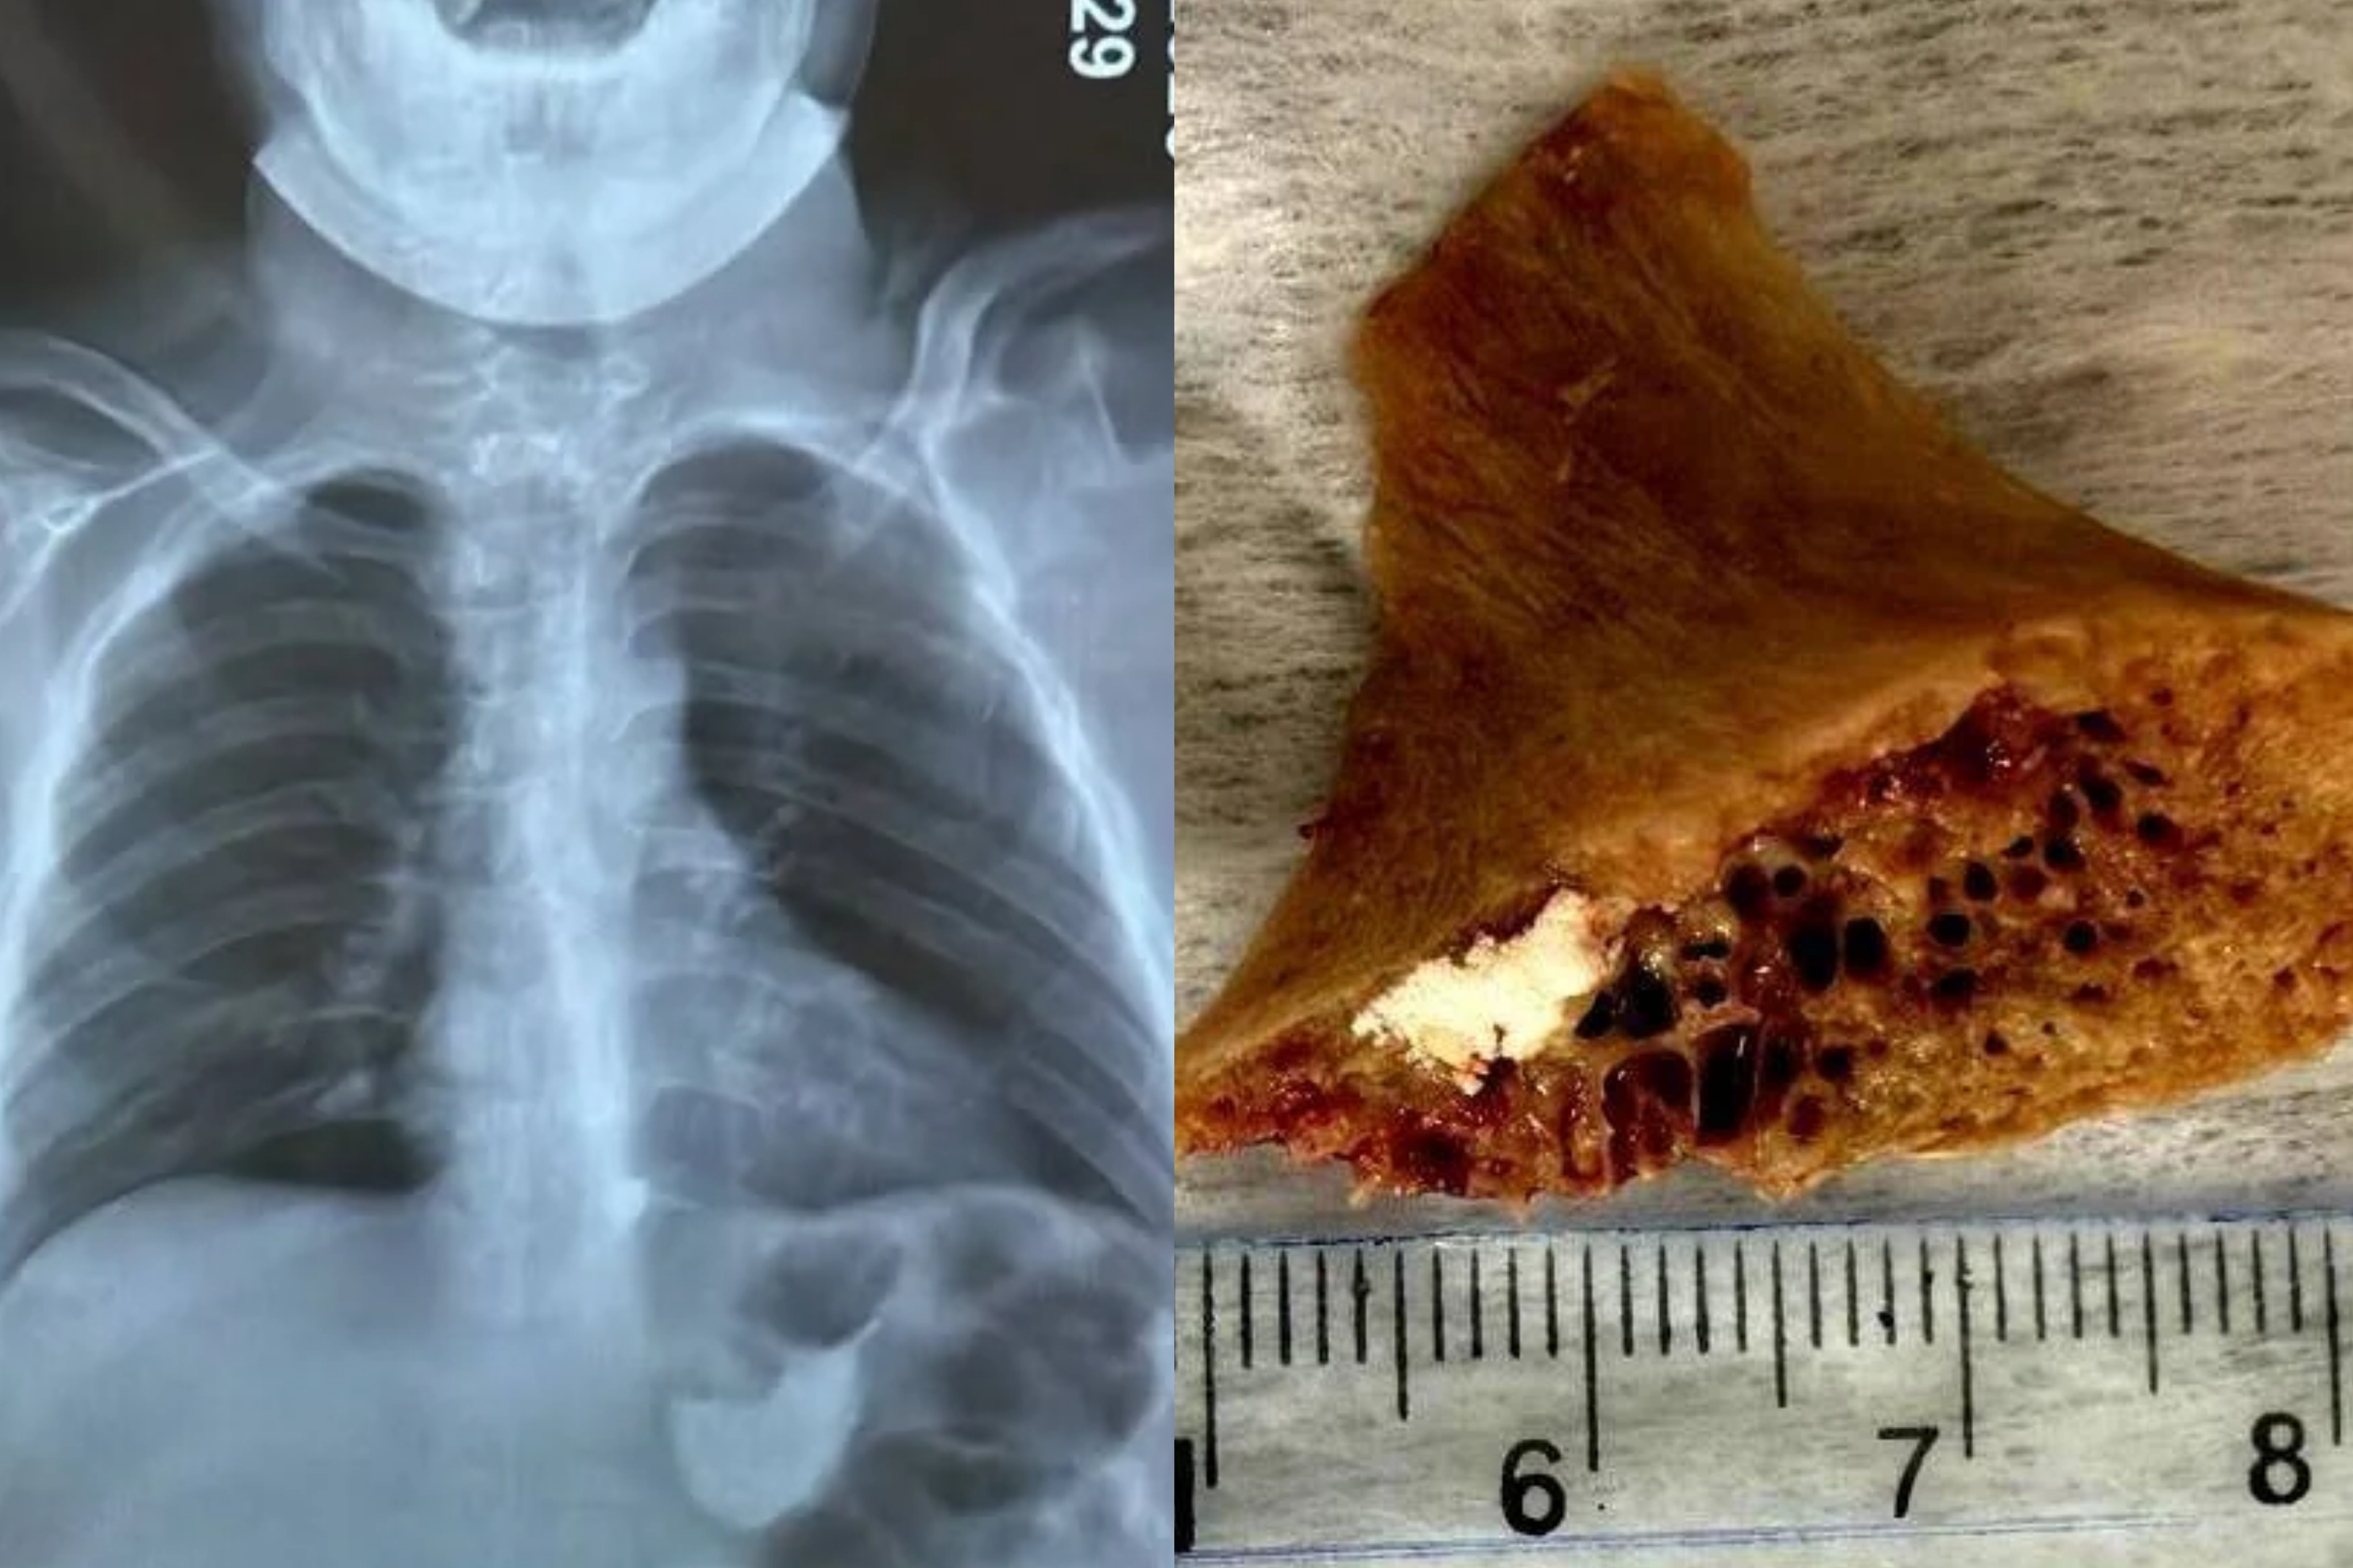

Маалыматка ылайык, бала 4 сантиметр өлчөмдөгү сөөктү жутуп алган. Шаардагы эки ооруканада сөөктү чыгара алышпагандыктан, бала Бишкек шаардык медициналык тез жардам балдар клиникалык ооруканасына жеткирилген.

"Дарыгерлер ыкчам түрдө операция жасап, тыгылып калган сөөктү ийгиликтүү алып чыгышты. Оор абалда келген балага дароо керектүү медициналык жардам көрсөтүлүп, операцияга жасалды", - деп белгилешти ооруканадан.